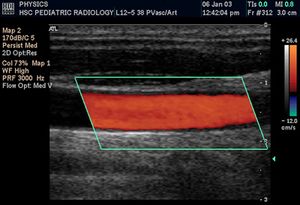

- 컬러 도플러: B 모드 영상 위에 특정 영역 내 혈류의 평균 속도와 방향을 색상으로 표시한다. 일반적으로 탐촉자로 다가오는 혈류는 붉은색 계열로, 멀어지는 혈류는 푸른색 계열로 나타낸다. 이는 물리학에서 적색편이가 멀어짐을, 청색편이가 가까워짐을 나타내는 것과는 반대이다. 컬러 도플러는 혈류의 전반적인 분포와 방향을 직관적으로 파악하는 데 유용하다.